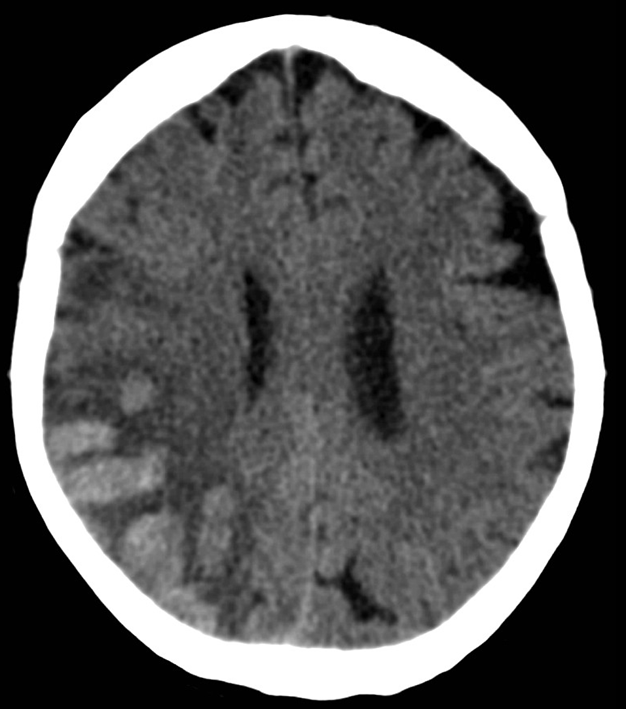

15.2.2.2. In skull trauma

The key question whether the patient ha intracranial hematoma, which causes mass effect and later leads to vasoconstriction. In the presence of open skull fracture signed by liquorrhea severe infection and herniation might occur. To exclude intracranial hemorrhage CT is the modality of choice.

All three types of intracranial hematoma can occur as a result of head trauma:

• Subdural bleeding is caused by injured bridging veins (elongation, tears) e.g. when a sudden deceleration occurs. This type of injury generally is not associated with a fracture.

5. A middle aged chronic alcoholic male. On unenhanced CT a typical crescent shape subdural hemorrhage is seen on both sides. Because of its etiology it extends across suture lines.